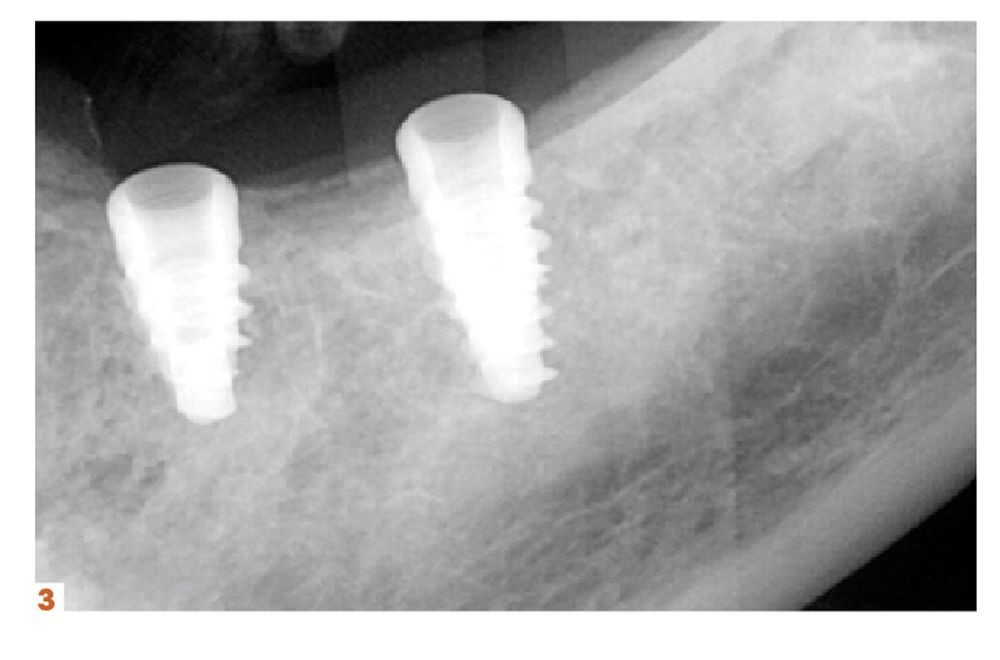

Garvin thinks that implementing CBCT 3D technology is essential for practice productivity growth. Planmeca’s Ultra Low-Dose™ provides a safer way for clinicians to get a 3D image and a better clinical diagnostic solution, he explains.

“We’ve successfully driven down radiation levels so that they’re the same or less than an intraoral x-ray. Now, clinicians can get a 3D image of that anatomy of a patient’s tooth, and they can completely change how they diagnose right from the start,” Garvin says. “We also see case acceptance rates going up because now that patient can connect with something that looks more like them than a flat, 2-dimensional x-ray.”

Klein agrees that practices should invest in 3D imaging. However, he also thinks dental professionals should assert their expertise and in-office solutions for patient care, from investing in technology that facilitates in-office solutions that respond to patient demands to incorporating digital workflows.

“They should invest in technologies that allow them to offer things like same-day dentistry or even just faster, more convenient dentistry,” Klein says. “It goes back to creating that positive patient experience that also comes with better clinical outcomes.”

Imaging can help dentists see opportunities, too. Garvin recommends clinicians get a baseline CBCT education and take a course on reading a scan from a radiologist. Regarding equipment, Garvin suggests understanding which field-of-view size will accommodate the kind of dentistry the dentist does now, and what they might like to add in the future. He also recommends dentists do their research by validating manufacturer’s claims and looking for evidence-based features and how they support both patient care and efficient workflows.

“Also, get into a platform that allows the machine to grow with your needs and move at your pace with machines that are upgradeable and updatable,” Garvin says.